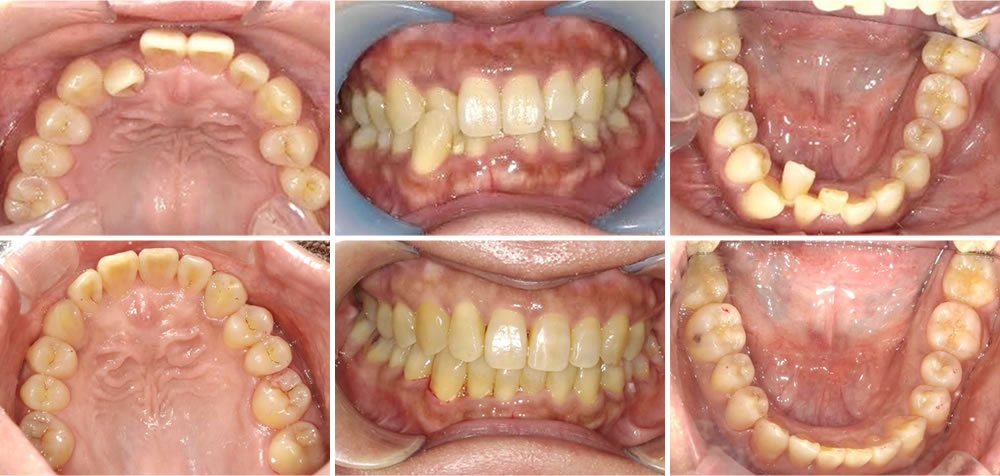

インビザラインで過蓋咬合・前歯の叢生を改善した症例

こちらの患者さまは前歯の反対咬合とガタツキが気になると言う事でインビザラインによる矯正治療を行いました。

歯が重なりあってガタガタしていると歯磨きも困難になる為、歯周病のリスクも高くなります。矯正治療にて歯並びを綺麗にしたことで、見た目の改善に加えて歯を磨きやすくなったと喜んで頂くことができました。